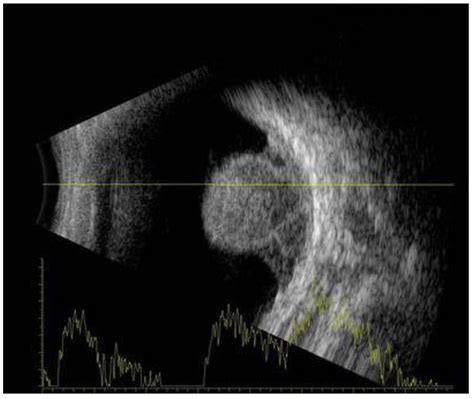

Bone Bone Lump Near Collar